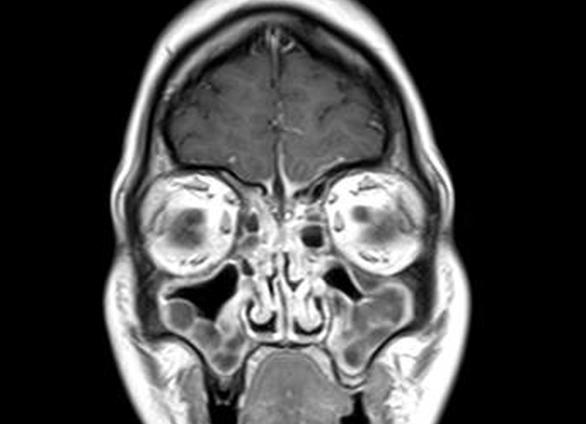

Мрт околоносовых пазух

Магнитно-резонансная томография (МРТ) придаточных пазух носа

Придаточные пазухи носа выступают своеобразным фильтром для защиты человеческого организма от инфекций, пыли и других внешних факторов. Орган подвержен множеству заболеваний – от врожденных дефектов до кист или полипов. Для быстрой и эффективной диагностики врачи назначают магнитно-резонансную томографию. Чем хорошо метод, в каких именно случаях назначают МРТ и чего ждать от процедуры?